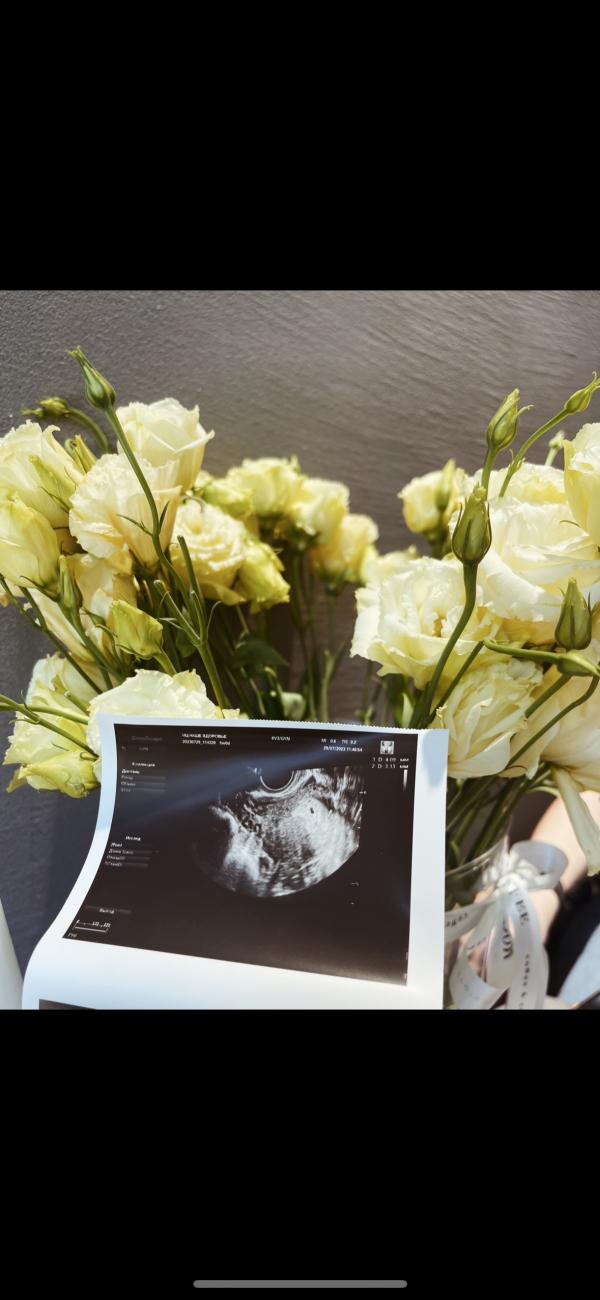

Мой малыш родился бы в октябре 2023, но замер на 11й неделе😩

В июне узнала о беременности, пдр был бы 08.03.2024, но 9 августа узнала что моя бусинка замерла